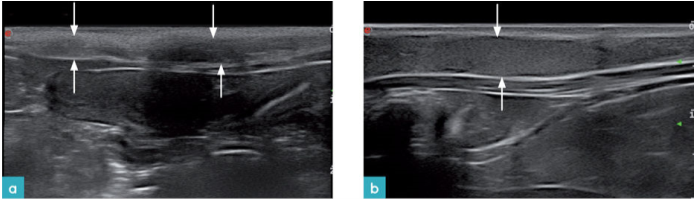

由于正常浅表淋巴结的回声强度与脂肪的回声相近,所以在正常至偏胖体型的猫身上,较难辨认出浅表淋巴结。淋巴结回声强度略高于脂肪回声强度,或与其相当(图8)。部分淋巴结,尤其是在腘淋巴结和颈浅淋巴结上,淋巴门处回声偏高,在影像上看起来像是淋巴组织包裹着脂肪。该特征有助于区分出淋巴结,外周还可见高回声的淋巴结被膜。

目前没有所有淋巴结的正常测量参考值。参考解剖数据背侧颈浅淋巴结长度约为3.2cm,腹侧颈浅淋巴结的长度约为0.08-1.46cm;腋淋巴结和腋副淋巴结的长度约为1.95cm;腘淋巴结的长度小于1.2cm,腹股沟浅淋巴结长度约为1.95cm。一份超声研究报告中指出,健康猫的腘淋巴结短轴长度约为0.28-0.65cm,而长轴长度约为0.43-1.20cm。